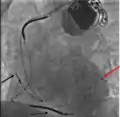

Електрокардіостимуля́тор — це пристрій, що виконує завдання штучного синоатріального вузла серця (або кардіовертер-дефібрилятор), який імплантується (вживляється) людині з метою відновлення та нормалізації порушень ритму серця.